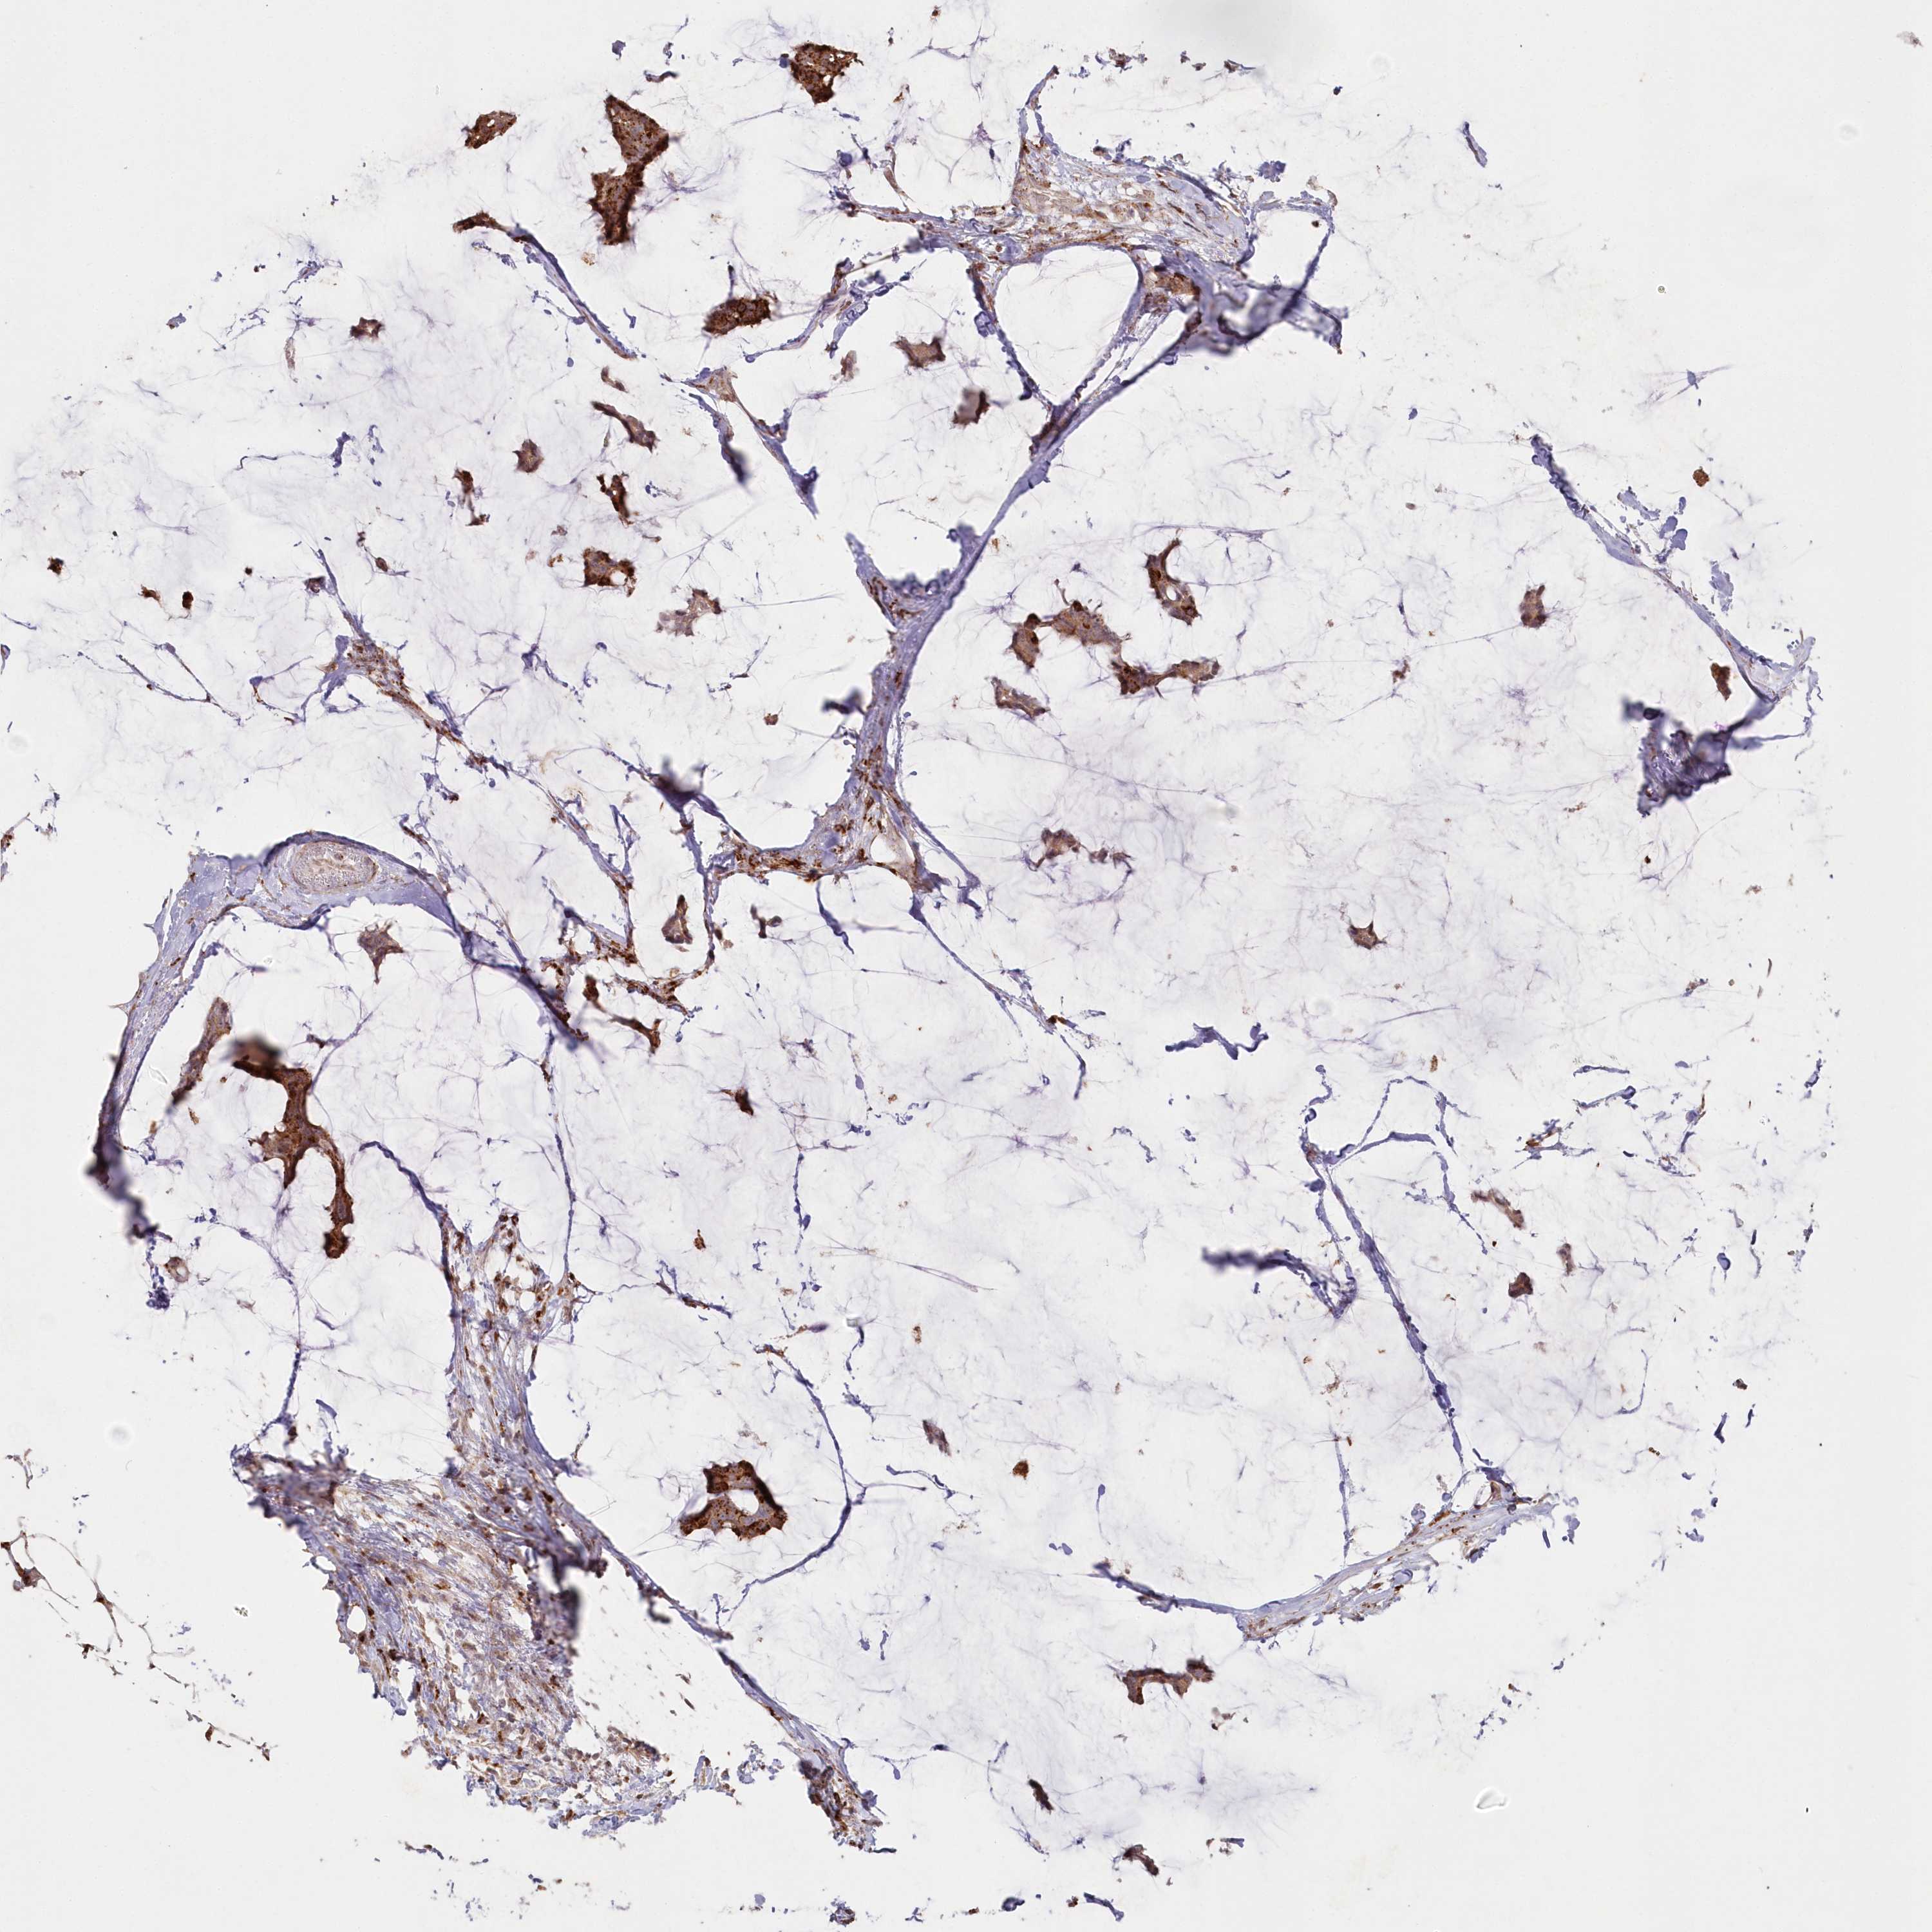

CANCER BREAST CANCER Show tissue menu

BRCA TCGA BRCA VALIDATION PROTEIN EXPRESSION